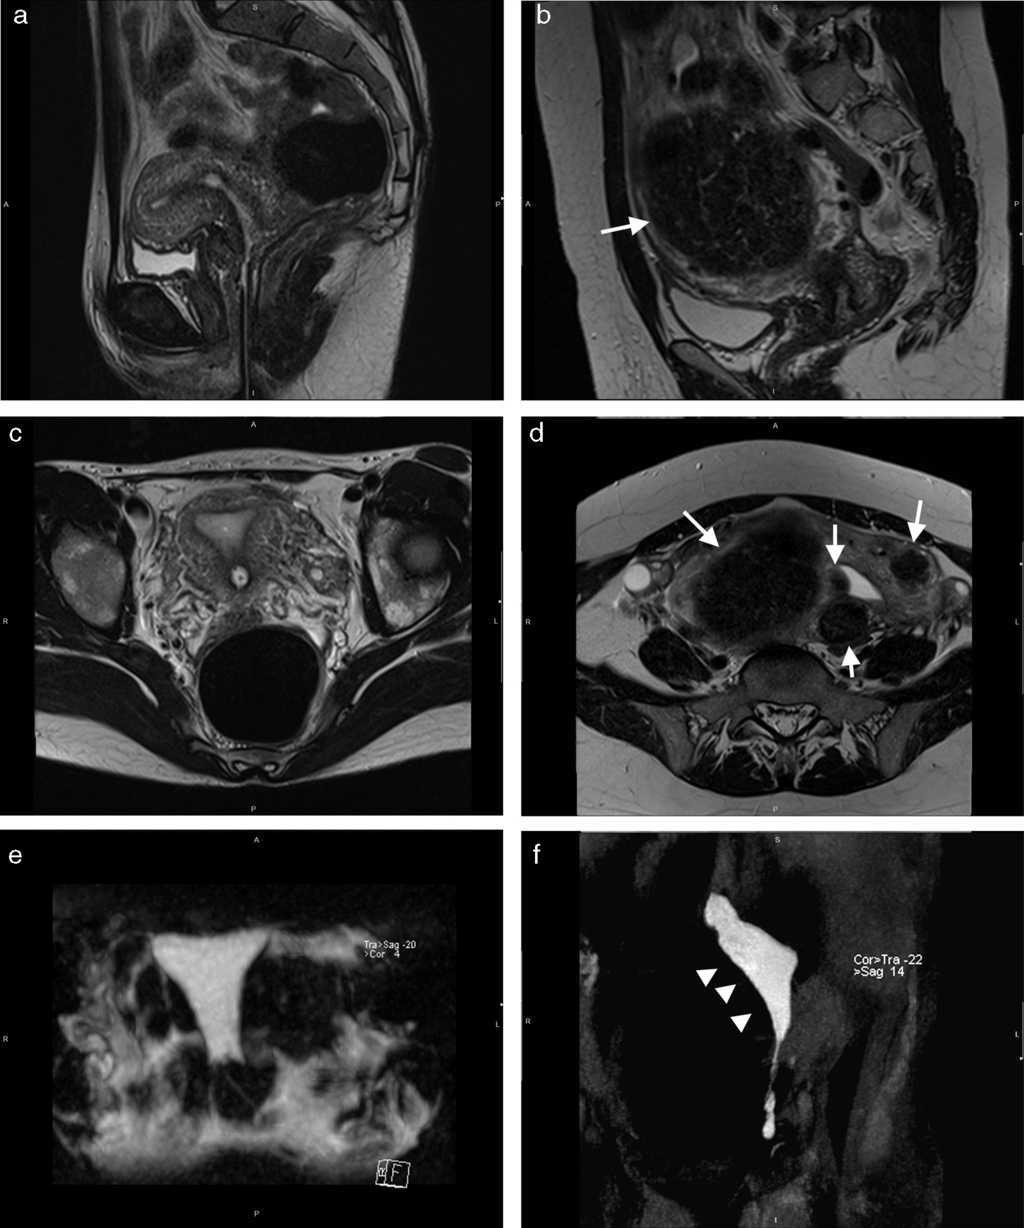

El volumen inyectado fue significativamente diferente entre las pacientes con un útero aumentado de tamaño por leiomiomas y aquellas con un útero de tamaño normal (fig. 2; tabla 2). El tiempo de exploración y el dolor no variaron significativamente.

Nuestros resultados iniciales en el rendimiento diagnóstico de la HSG-RM para la evaluación de la permeabilidad tubaria han demostrado una alta sensibilidad y especificidad en comparación con el verdadero método de referencia para esta evaluación, la laparoscopia con cromotubación (figs. 1 y 3). Aun cuando se consideró cada trompa de Falopio por separado, y pese a no poder visualizar en algunas pacientes el contorno mismo de la trompa, se observó una alta sensibilidad y especificidad para la trompa izquierda y una alta especificidad para la derecha. La causa de la baja sensibilidad observada en esta última aún se desconoce y amerita más investigaciones con una muestra poblacional más grande.

Además de permitir la visualización de la permeabilidad tubaria sin yodo ni radiación, la HSG-RM ayudó a detectar enfermedades previamente desconocidas en la población en estudio, tal como han referido estudios previos11. Específicamente en nuestro caso, en hasta el 23% se detectó una afección que las pacientes desconocían tener (lo que refuerza la capacidad potencial de este procedimiento para convertirse en el único examen requerido para las pacientes con problemas de fertilidad). Asimismo, la mayoría de los hallazgos informados en la HSG-RM se correlacionó con los informados en la cirugía. Solo se encontró una baja correlación de la HSG-RM con la cirugía en el caso de las adherencias peritoneales, ya que no se pudieron detectar las adherencias delgadas mediante las secuencias de RM, con lo cual hubo una subestimación de la endometriosis pélvica.